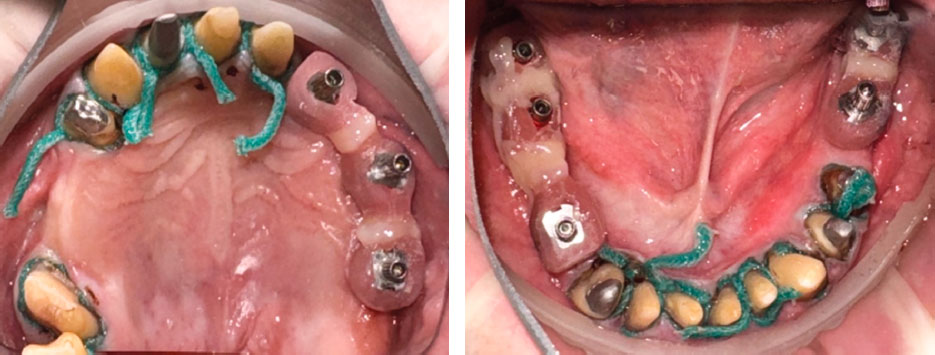

Произведено препарирование зубов под искусственные коронки (рис. 10).

Рис. 10. Зубы, обработанные под искусственные коронки

Пациенту проведена ретракция десны, использована методика двойных нитей. Трансфер-чеки соединены композитным материалом (рис. 14).

Рис. 14. Установлены ретракционные нити и трансфер-чеки соединены композитным материалом